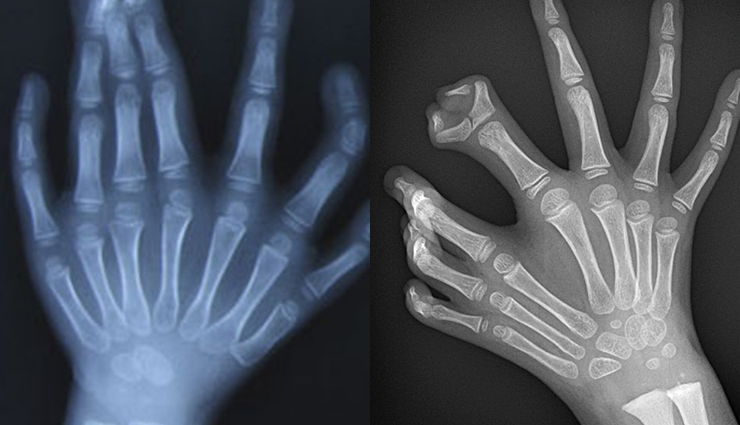

Mirror hand syndrome manifests in a spectrum of severity, ranging from mild to severe duplication. In instances of mirror-image duplication of the ulna, two ulnas are present on the affected side, and the digits may also be duplicated, resembling a mirror image of the corresponding hand.

Ulnar dimelia often coexists with other limb abnormalities, characterized by the absence of the radius, duplication of the ulna, and symmetric polydactyly. Common features include syndactyly (fusion of fingers) and polydactyly (extra fingers), with possible skeletal deformities in the hand and forearm.

# Imaging Studies:

X-rays, CT scans, or MRI scans may be used to obtain detailed images of the affected limb's bone structure, joints, and soft tissues.

These imaging studies help in visualizing the extent of duplication and any associated anomalies.